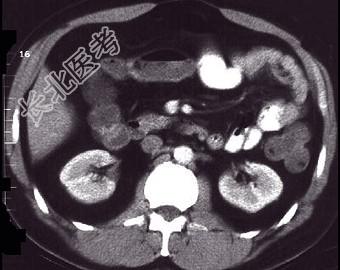

- 单项选择题女,30岁, 右下腹痛,腹泻便秘交替出现, 消瘦乏力,血沉加快, X线检查如图,最佳的诊断是 ( )

A、小肠癌

B、小肠结核

C、小肠克罗恩病

D、结肠癌

E、阑尾炎